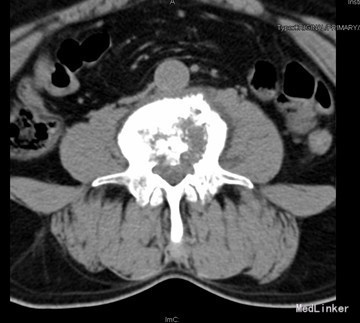

查体:腰4、5棘突轻度叩压痛,双侧大腿后外侧小腿外侧及足背感觉功能减退,以右侧明显。 辅查:CT示腰4椎体骨质破坏并增生、硬化改变,以骨质破坏为主,左侧椎旁软组织肿块形成,结核?肿瘤待排。腰4、5腰5骶1椎间盘突出。腰椎退行性变。MRI示腰4椎体骨质破坏,性质?腰4、5腰5骶1椎间盘突出,腰椎退行性变,双侧髂骨信号不均匀,性质?

初步诊断:腰4椎体骨质破坏:结核?肿瘤? 诊疗计划:经前路腰4椎体部分切除,椎管减压,取自体髂骨植骨融合,Antares内固定术

术中见腰4椎体骨质破坏,其内可见空腔形成,周围骨质硬化,左侧椎旁椎体空腔内可见少量干酪样坏死组织,腰3、4椎间盘破坏、碎裂,部分组织突入椎管,压迫硬膜囊,取坏死组织术中冰冻切片示:肉芽肿性炎症伴坏死。